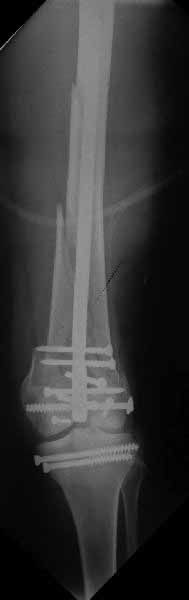

Здесь пример медиальной пластины и латеральный комбинированный метод (у второго больного старый перелом тибиал плато, леченный где то и когда то)

Ответ на эту часть Вашего поста – вложенный файл. Больная оперирована неделю назад по поводу открытого перелома дистального эпиметафиза бедренной кости. После операции она идёт в рентгенкабинет для выполнения послеоперационной контрольной рентгенографии, представленной на слайдах 10 и 11. Узнав, почему её фотографируют, просила передать Вам, Антон, привет.